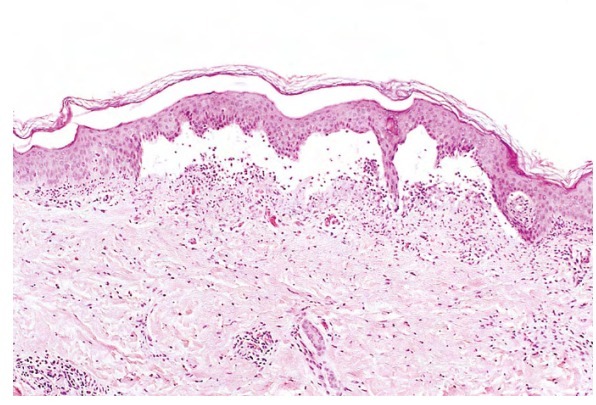

Ulcerações

A

Ocorrem quando há escavação, cavitação na superfície de um órgão. São consequência da necrose extensa, seguida do desprendimento dessa porção necrótica do tecido.

Podem ser encontradas na mucosa oral, intestinal e do trato genitourinário. Além disso, em inflamações subcutâneas de pessoas com distúrbios circulatórios, na qual a necrose é mais propensa.

Durante o estágio agudo, há um infiltrado polimorfonuclear, com aumento no calibre de vasos circundantes. Com a cronicidade, há a cicatrização das margens e da borda e o infiltrado adquire um aspecto de linfócitos, macrófagos e plasmócitos